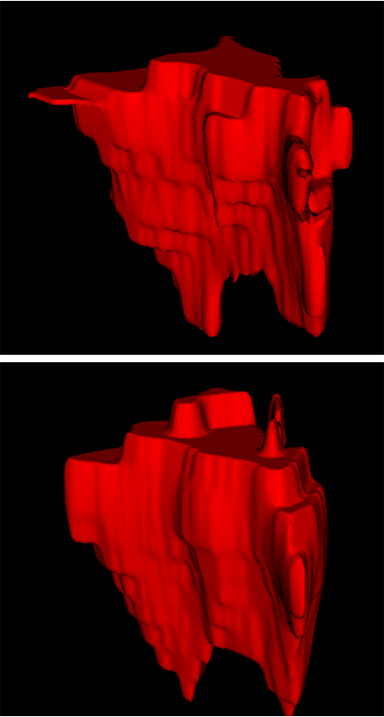

Comparison with ground truth. Some predicted results of MMFNet are shown in 2D images and 3D images in Figure 7 and Figure 8. As shown in these figures, although the shape and size of NPC are varied from each other, MMFNet can still accurately determine the regions of NPC and obtain the accurate contours of tumors. Through analyzing 2D images in figure 7, MMFNet has a capacity to fuse multi-modality MRI to reduce the confusion brought by intensity’ similarity between nearby tissues and NPC. The values of , and of MMFNet are shown in Table 1. MMFNet can reach the best results with , and .

Comparison with related works. Table 1 reports the values of , and for different methods. Predicted masks of different methods are illustrated in Figure 9 and Figure 10, which respectively present results in 2D and 3D images. Through comprehensively analyzing these results, the proposed MMFNet actually have the following properties:

(i) It directly fuses 3D MRI images rather than 2D slices. Thus, it can effectively use meaningful information from neighboring slices of MRI to realize NPC segmentation. As shown in Table 2, MMFNet can bring , and improvements in and compared to the best method based on 2D images (Multi-modality patch-based CNN). And Figure 10 shows that 3D-based methods have less isolated regions (false positives) than 2D-based ones.